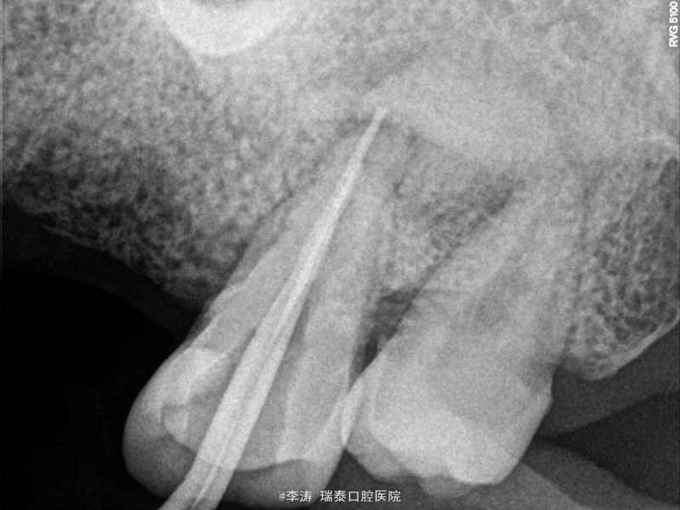

根尖区病变牙的治疗一例

牙骨质瘤 牙骨质瘤

26残冠 25,27根管治疗不到位 27牙根尖区高密度影 所有牙均无临床症状

经多方会诊,确认考虑27牙根尖牙骨质瘤,建议先行根管治疗,然后密切观察 予以拔除26,根管治疗25,27

几个问题 1,26牙修复方式是种植还是烤瓷桥,26如果种植,成功的几率大不大 2,27牙的预后会是怎么样,见得不多,望请赐教